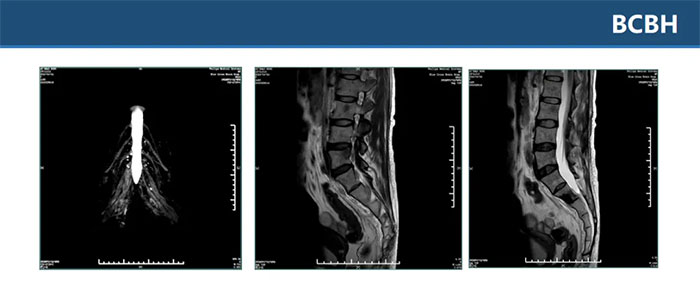

▲ 雙側(cè)骶叢神經(jīng)平掃+增強(qiáng)未見(jiàn)明顯異常,L2、L4、骶S1-3椎體及其附件區(qū)多發(fā)異常信號(hào)影